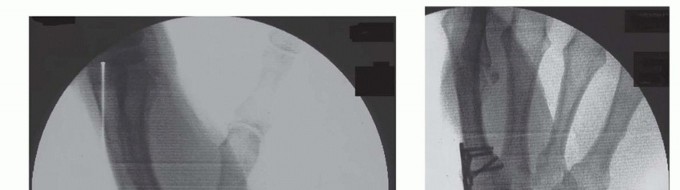

FIG 2 • A,B. AP (A) and lateral (B) fluoroscopic images demonstrating application of plate and screws across thumb CMC joint.